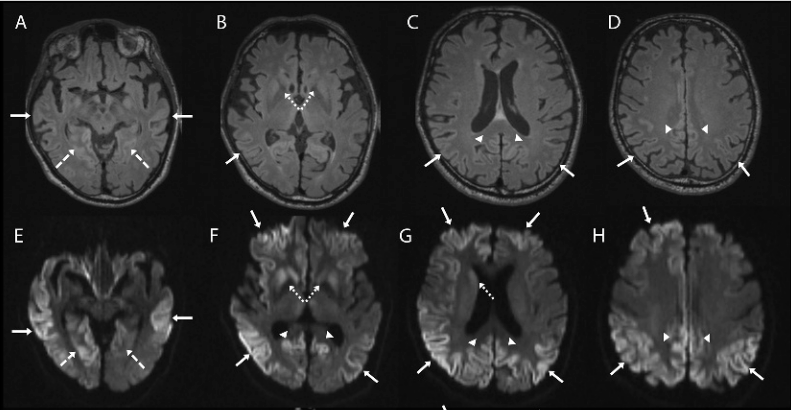

人类被朊病毒感染后会患上克雅二氏病,其症状和“哈哈病”极为相似。

正常来说如果人体内含有的少量朊病毒,会让人体的“防御部门”制造相应的“防御兵”,来抵挡朊病毒的进攻,原理和疫苗一样。若是大量的朊病毒同时进入体内,“防御兵”没有足够的兵力阻挡“外敌”入侵而战败,最终被朊病毒入侵的人也会患上克雅二氏病。

患者在感染的前几周会出现小幅度的性格改变,以及头晕、失眠、抑郁等症状。随着病情的恶化,就会开始出现肢体僵直和震颤、语言障碍等,并迅速发展为精神衰退、半瘫、惊厥、昏迷等。最终死于肺炎或自主神经功能衰竭。诱发克雅二氏病的朊病毒可以长期潜伏,等待度过潜伏期后,迎接患者的就是无尽的痛楚,最终伴随着自己的笑声走向生命尽头。据不完全统计,约90%的患者在发病后1年内死亡。